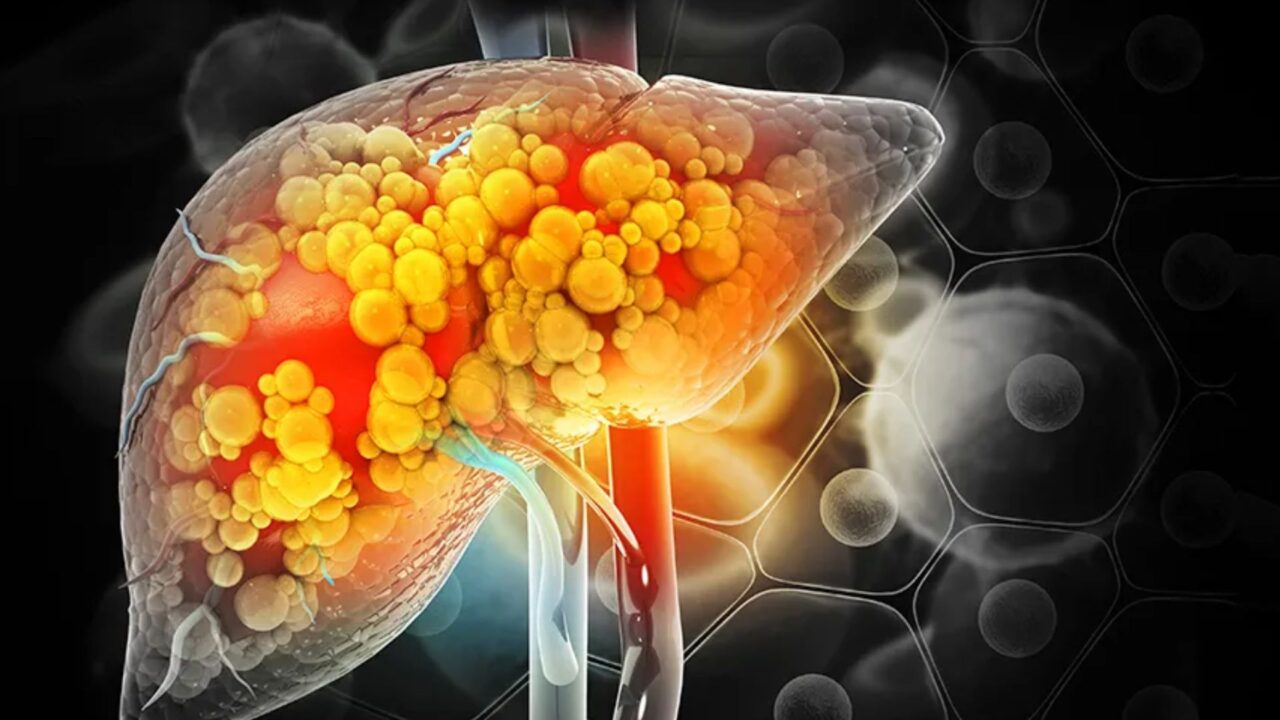

En el caso del primero, se acumulan altas cantidades de grasa en el hígado. Esto, con el paso del tiempo, irá provocando problemas en la salud. Por otro lado, el segundo surge cuando el exceso de grasa provoca inflamación y cicatrización en el órgano. Cuando es grave, se puede derivar en cirrosis o cáncer de hígado.

Como ya se mencionó, si bien estos padecimientos tienen relación estrecha con pacientes obesos, la FundHepa refiere que los pacientes no obesos están aumentado. Por ejemplo, aunque hay alto índice de personas delgadas en los países delgados, entre el 5 y 26 % tienen NAFLD. Además, la gravedad de estos padecimientos no necesariamente disminuye en pacientes no obesos.